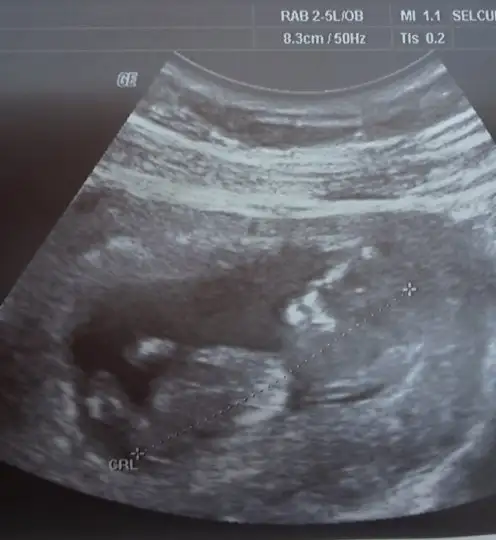

Bunlarda benim minik bebişim 3 boyutluda baktı cok güzeldi hiç durmadı sürekli eller kollar hareketliydi :) bebeğimin durumu cok iyiymiş 2li test için kan verdik çarşamba gününe cıkacakmış. ama doktorum memur olmuş baska bi yere atanmış gidiomuş :( yeni doktor bulmam gerekio nası bulcam nası karar verecem bilmiorum :( cinsiyetini göremedi bacaklarını kapatıyor dedi çarsamba testleri göstermeye gittiğimde yeniden bakmasını isticem bakalım gösterecekmi:) raporisticektim ama kötü haberi alınca bişi diyemedim :(:(